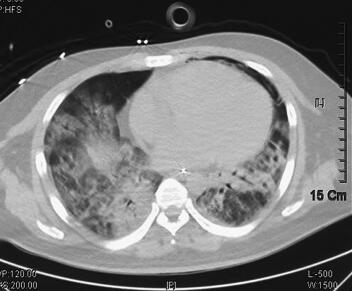

诊治经过:入科后立即予经口气管插管接呼吸机辅助通气,模式为BiPAP,参数为:FiO2 80%,Tinsp 0.95秒,PIP 30cmH2O,PEEP 15cmH2O,f 25次/分,呼吸急促,人机拮抗明显,予丙泊酚、咪达唑仑镇静,吗啡镇痛,间断维库溴铵肌松、扩容,亚胺培南-西司他汀钠1.0g静脉滴注,每8小时1次,莫西沙星400mg静脉滴注联合抗感染,乌司他丁、甲泼尼龙抑制炎症反应,氨溴索化痰,去甲肾上腺素维持血压及对症支持处理。治疗3天后患者临床症状改善不明显,高浓度给氧下氧饱和度维持在80%~85%,但患者部分炎症指标(BRT、CRP、PCT)进行性好转。考虑到患者病情危重,继续予机械通气支持,同时加大镇痛及镇静药物用量,减少患者氧耗。至4月8日血压仍需升压药维持,实验室检查NT-ProBNP 2084pg/ml,cTnI 0.35ng/ml,4月9日床边超声心动检查示心脏各个腔室大小正常,EF 45%,舒张功能减低,提示心功能不全,心肌损害。经过治疗,患者体温、BRT、CRP在入科治疗后即呈逐步下降趋势,至4月11日体温下降至正常范围,停用升压药物,血压维持120/75mmHg左右,呼吸机参数逐步下调,经皮氧饱和度维持在94%~96%左右。随后患者多次痰培养检出热带假丝酵母菌(4月7日、4月9日、4月11日、4月14日);因患者血液炎症指标逐渐下降,体温逐渐恢复正常,并无继发真菌感染的依据,考虑为定植菌可能,故未予抗真菌治疗,同时于4月12日停用亚胺培南-西司他汀钠,改用头孢哌酮-舒巴坦钠3.0g,每8小时1次,此后血常规检查血白细胞进行性升高,至4月17日白细胞计数22.72×109/L,并出现体温升高,至17日最高38.1℃,4月16日开始氧饱和度较前有所下降,波动在88%左右,尤其在吸痰后呼吸急促伴氧饱和度下降,遂予加大呼吸机支持力度,给氧浓度为60%,PEEP 14cmH2O,PSV 10cmH2O,RR 20次/分,Tinsp 1.1秒,SaO2维持在89%~94%。考虑已出现二重感染,继发肺部真菌感染可能性较大。4月17日加用氟康唑400mg每12小时1次,抗感染治疗,第2天400mg,每日1次。4月18日患者呼吸急促加剧,经加大镇静治疗及加强呼吸机支持均效果不佳,氧饱和度下降明显,只能维持在70%~80%左右;同时查血常规白细胞及CRP较前升高,两次半乳甘露聚糖试验(GM试验)回报结果阳性。临床考虑曲霉感染,予停用氟康唑,改用伏立康唑,继续加强镇静镇痛治疗,更改抗生素第2天晚上患者情况趋于稳定。之后患者体温下降,4月21日恢复至正常范围,呼吸情况逐渐改善,并能逐渐减少镇静药物剂量、下调呼吸机支持力度,同时WBC、CRP及PCT等炎症指标逐渐下降。4月25日复查胸部CT提示两肺感染较前吸收;4月25日复查超声心动图提示各个腔室大小正常,EF 65%,舒张功能减低;cTnI < 0.1ng/ml,NT-ProBNP 84pg/ml。4月26日发现胸壁皮疹,考虑为药物副反应可能,为伏立康唑的药物副反应所致,改用伊曲康唑继续抗曲霉治疗,患者皮疹逐渐消失,患者病情继续改善。至5月4日呼吸机改为CPAP模式,5月5日顺利停用呼吸机,予气管切开给氧,并停用全部鼻饲,经口进食,复查胸部CT提示双肺感染较前有所吸收,左下肺多发空洞形成,并转出ICU(图2)。5月10日,改为伏立康唑片剂序贯治疗,患者未出现皮疹以及其他不良反应,5月15日复查超声心动图提示各个腔室大小正常,EF 70%,舒张功能减低。5月20日肺功能检查提示重度限制性通气功能障碍。5月24日出院。6月8日复诊,患者自觉良好,无胸闷、气促,无发热,无咳嗽、咳痰,复查胸部CT双肺感染明显吸收、好转,左下肺空洞形成(图3)。继续服用伏立康唑片剂约2个月后停药,随访至今患者自觉良好,能够正常生活以及工作。

图2 2011年5月5日胸部CT示双肺感染较前明显好转,左下肺空洞形成